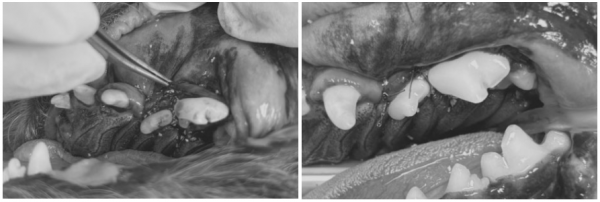

[진행한 치아 치료 과정 GBR/GTR(치조골 재생술)]

치아를 보존할 수 있는 좌측 어금니 부위는

다음과 같은 방식으로 보존 치료를 시행했습니다.

→ 해당 치아의 잇몸을 분리 후,

염증 조직을 제거하고 치은연하 스케일링을 진행한 뒤

→ 뼈 이식재를 해당 부위에 이식하고

차폐막을 삽입한 뒤 안전하게 봉합하였습니다.